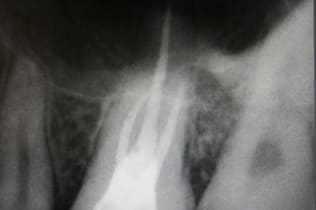

根管治療は無菌の根管を作り、緊密な根管充填が絶対条件です。歯の寿命がこれで決まると言っても過言ではありません。下の写真は根管充填不良により引き起こされた、根尖性歯周炎の状態です。左が根管治療前、右が根管充填後のレントゲン写真。

術前

CWCT法による根管治療の術後